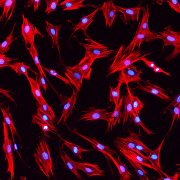

Levínský kocour |  Která buňka ztrati... |  Stojící keratinocy... |  Odraz fibrinového a... |